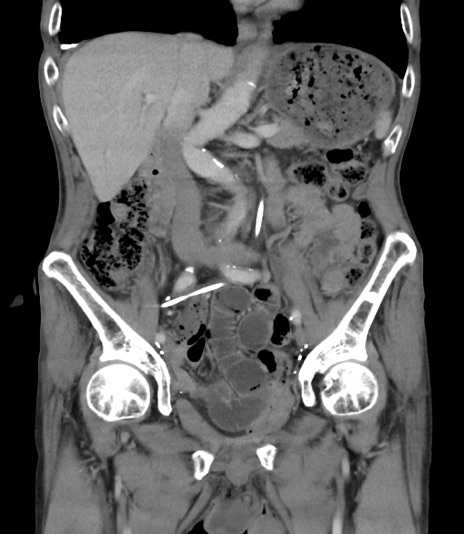

症例3(冠状断像)

【症例】 70歳代男性

【主訴】右鼠径部腫瘤、疼痛

【現病歴】本日朝より上記主訴あり、受診。

【既往歴】膀胱癌にて膀胱全摘、両側尿管皮膚瘻

【データ】WBC 5600、CRP 0.56